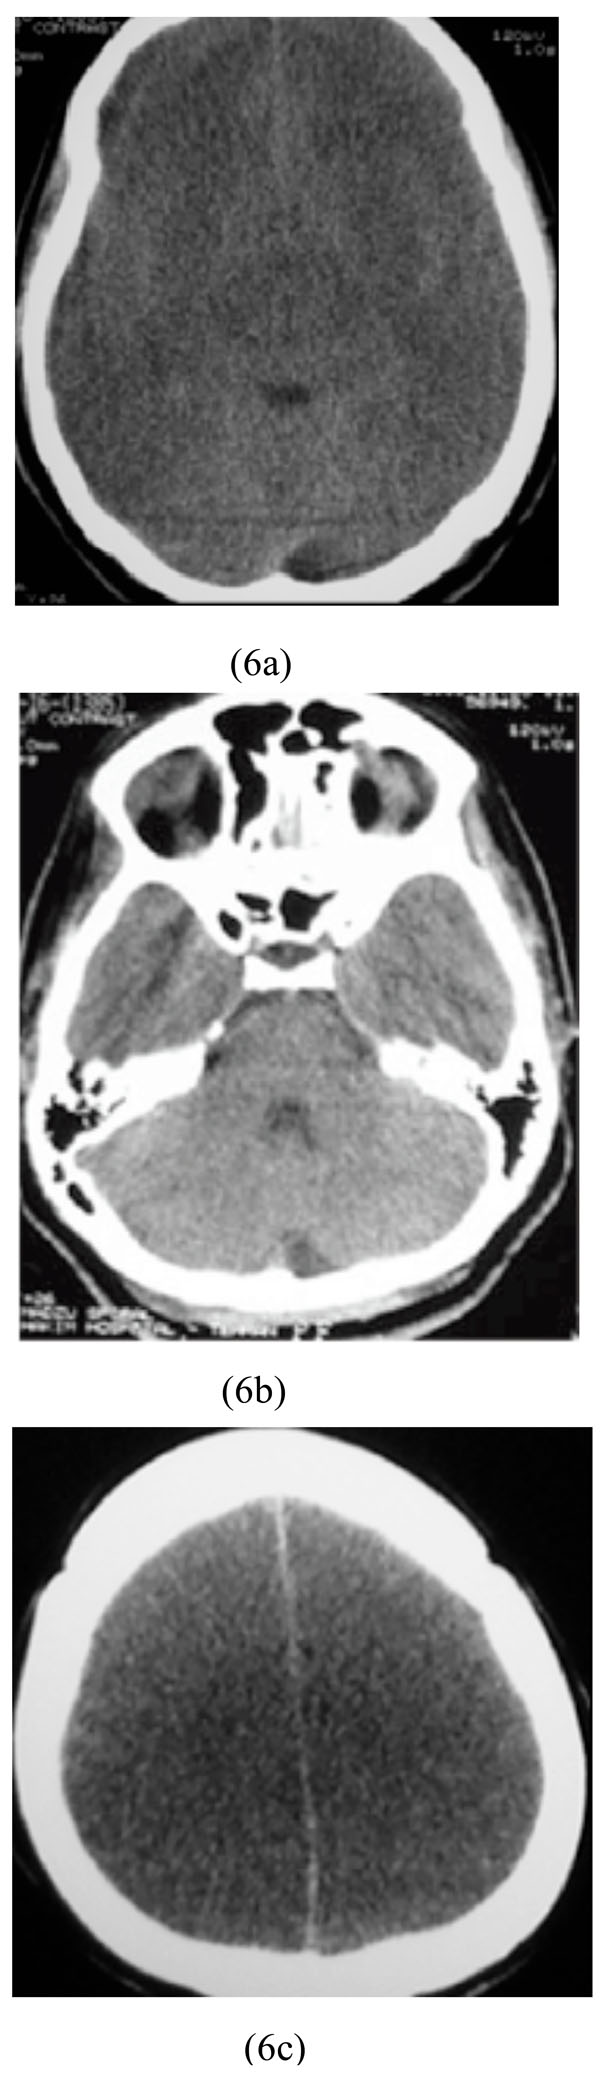

A 27-year-old woman, previously diagnosed by major depression, who decided to commit a suicide, was brought to our hospital three hours after ingestion of 750 mg of amitriptyline. On physical examination, her BP was 150/90 mmHg, PR of 110/min, and RR of 12/min. Laboratory data revealed a metabolic acidosis with no abnormal blood glucose or electrolyte levels. Electrocardiogram revealed tachyarrhythmia. Brain CT scan showed diffuse supratentorial cytotoxic edema with sparing of infratentorial region (Figs. 6a-6c).

Diffuse supratentorial cytotoxic edema with sparing of infratentorial region associated with amitriptyline poisoning.